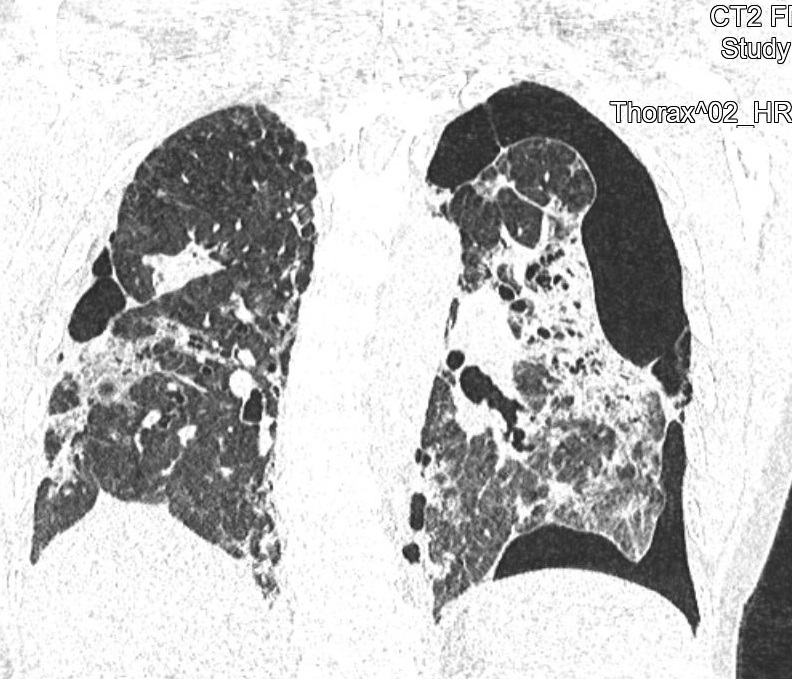

CT snímky vývoje patologických změn na plicích po prodělané nemoci covid-19 u třiapadesátileté doposud zcela zdravé pacientky (fotografie CT nálezu publikovány se svolením Dr. Evy Kočové, Ph.D. – RDG klinika):

Obr. 3: V červnu 2021 se situace komplikuje oboustranným kolapsem plíce s pneumotoraxem – přítomnost vzduchu z perforované plíce (zcela černé oblasti vpravo a zejména vlevo).